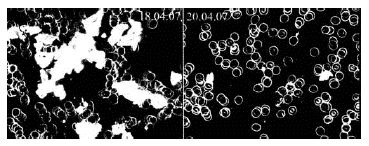

Рис. 18. Левая фотография демонстрирует склеивание тромбоцитов у больного, принимающего антитромбоцитарный блокатор ASS, нормализующий показатели крови по результатам лабораторных анализов. Картина «живой черной микроскопии» показывает, однако, на фотографии слева выраженную агрегацию тромбоцитов, которая исчезает через 2 недели питья живой воды (фотография справа). Источник: исследования (архив) доктора Ирлахера.

Иллюстрация к книге — Живая и мертвая вода — совершенное лекарство [i_005.jpg]

Две последние фотографии особенно наглядно показывают, что применение живой воды предотвращает сгущение крови, которое может способствовать возникновению инсультов и инфарктов. Наш опыт применения живой воды показывает также эффективность ее использования у больных с феноменом Рейно и перемежающей хромотой (боли при ходьбе), что тоже очевидно связано с улучшением кровообращения.